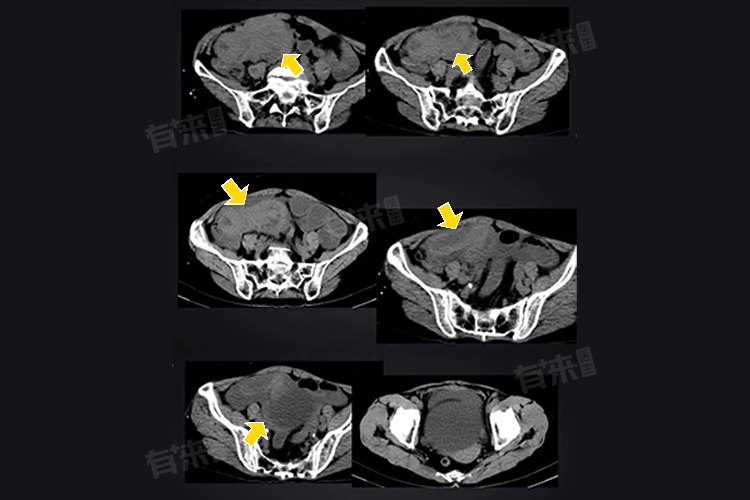

- 定期复查:严格按医生要求定期复查,如肠镜、CT等检查,及时发现肿瘤复发或转移迹象。若出现腹痛、便血、体重下降等异常,立即就医。